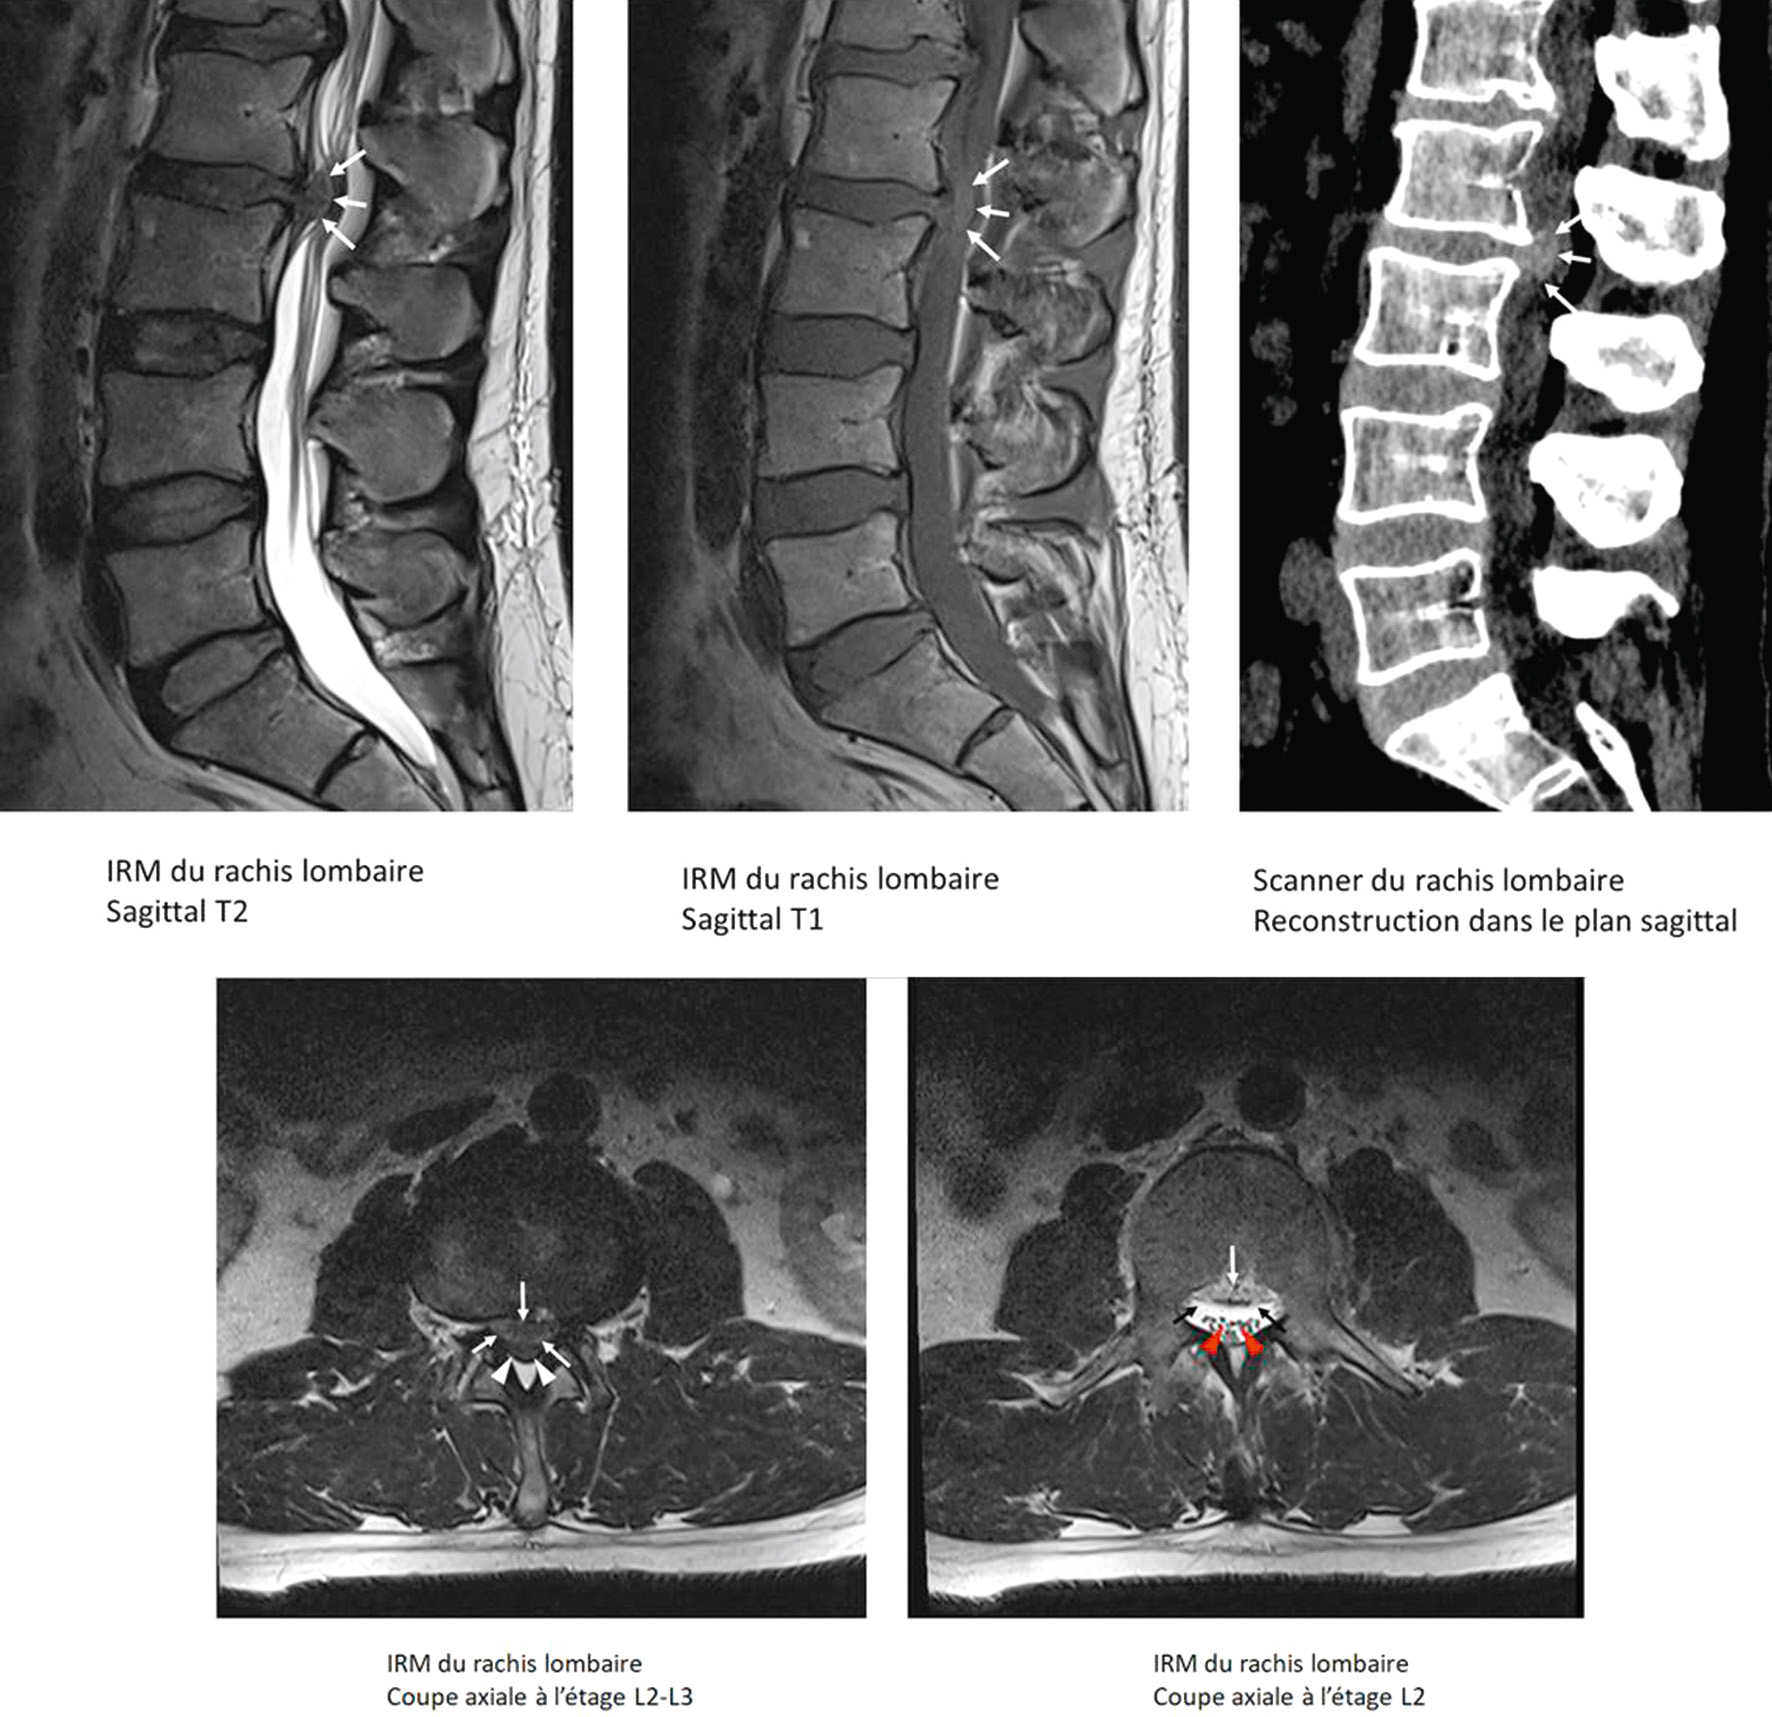

Les images combinées d’IRM et de scanner du rachis lombaire montrent une volumineuse hernie discale en L2-L3.

Fig. 8.7 Figure Hernie discale L2-L3 avec protrusion médiane ascendante réalisant une compression focale des racines de la queue de cheval à cet étage.

Coupes sagittales : délimitation de la hernie par les flèches blanches. Coupes transversales : T1 : hernie médiane (flèches blanches) et fourreau dural repoussé (têtes de flèches blanches). T2 : hernie médiane (flèches noires) et fourreau dural repoussé (têtes de flèches rouges).

En sagittal T2 (haut gauche), on observe une protrusion discale médiane ascendante avec déformation du sac dural. L’image T1 (haut centre gauche) confirme la perte de signal du disque, traduisant une dégénérescence. Le scanner (haut droite) met en évidence la protrusion calcifiée dans le canal rachidien. Les coupes axiales T2 (bas) à l’étage L2-L3 montrent une compression centrale du contenu canalaire, et l’image inférieure droite avec flèches rouges illustre la compression focale des racines de la queue de cheval. L’aspect global est celui d’une hernie discale comprimant directement les structures nerveuses centrales à ce niveau.